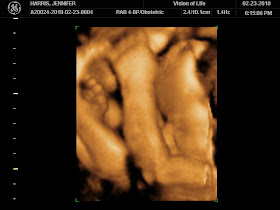

We watched our sweet babe wiggle around for over 30 minutes but I could have sat there all evening! He was being so active and we just kept waiting for him to show us his little face, but he wanted those little arms and knees by his face the whole time.

Babe is currently in a transverse position but the tech said she hoped that in a couple weeks, when baby has hopefully moved to a more head down position, he might not have as much room to bring his little hands and knees up to his face. Luckily they are letting us come back for FREE in two weeks to see if we can get a better look!

Baby all curled up in a little ball...you can see his fingers and toes in the same picture!